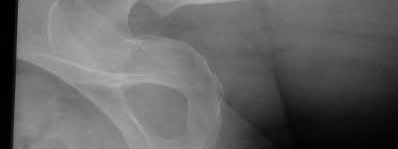

A 76-year-old male community ambulatory presented to clinic complaining of pain in the left groin that has been persistent for the last 8 months. Radiographs obtained from clinic are seen in Figure A. You suspect a femoral neck nonunion and obtain a CT scan which confirmed it. Which of the following statements is true?

A total hip arthroplasty (THA) after nonunion of a femoral neck fracture would provide the best long term outcomes in a 76-year-old male who is a community ambulator.

After nonunion of a femoral neck fracture, hemiarthroplasty and THA are good salvage option for the physiologically older patients. When deciding between these two options, THA is better for active and cognitively intact patients. THA is also indicated in patients with radiographic evidence of degenerative disease about the acetabulum. Hemiarthroplasty is advocated for patients who are older and less active.

Yang et al. retrospectively investigated the risk factors for nonunion in patients treated with cannulated screws. They reviewed 202 patients who had femoral neck fractures and were treated with internal fixation with cannulated screws. They identified that triangle configuration, displaced fracture, borderline or unacceptable reduction, and increased screw shaft subchondral purchase over the femoral neck were all risk factors for nonunion after internal fixation.

Inverted triangle configuration was found to increase rate of union.

Archibeck et al. retrospectively reviewed the outcomes of 102 THAs after failed internal fixation for a hip fracture (including both femoral neck and intertrochanteric). They concluded that the conversion of failed hip internal fixation has elevated risks compared to a primary THA, however, it may still be successful. The biggest concern for these patients postoperatively are periprosthetic fracture and dislocation.

Figure A is an AP pelvic radiograph demonstrating a nonunion of a femoral neck fracture after suboptimal fixation with 3 cannulated screws in a triangle configuration.

Illustration A is an AP radiograph of the left hip in this patient following conversion to THA.

Illustration B is a radiograph demonstrating a valgus osteotomy. Illustration C shows an example of a femoral neck nonunion with varus malreduction.

Answer 2: Varus reduction is closely correlated with failure in this fixation method.

Answer 3: The patient's best outcome would be with THA.

Answer 4: This would be a good option in a younger patient, but given age and functional capacity, the best option is THA.

Answer 5: Patients with hemiarthroplasty have lower rates of dislocation.